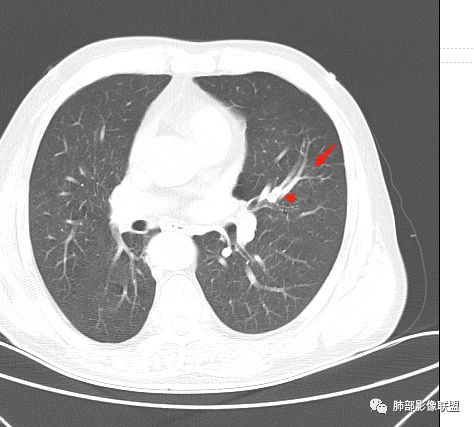

影像学特点:肺气肿背景下在大概一年的时间里出现了一个光滑的小结节,因为图像给的不是太薄,与支气管的关系判断不清,从结节周围出现斑片状炎症来判断,应该考虑结节位于支气管内,周围是阻塞性炎症,这样比较容易解释咯血

纵隔窗上似乎结节内可见点状高密度影,同时没有明显肿大淋巴结

所以我考虑支气管内的恶性肿瘤,类癌可能大。

左肺上叶小结节病灶,形态规则,边缘光滑,密度至密,远处阻塞性肺炎,病灶与支气管关系密切,给图太少不好观察,考虑神经内分泌癌(类癌),其次鳞癌

左肺上叶光滑结节影 似乎与支气管没有关系  ,给的纵隔窗病灶中心似乎点状钙化  病灶旁有更小结节,与上一年片比较 结节增大明显  考虑恶性 类癌可能

老年男性,肺气肿基础。约一年时间出现左肺上叶舌段支气管近端结节影,远端斑片样阴影,边缘模糊。考虑近端恶性占位,远端有阻塞性炎症。

老年男性,有咳血病史,左肺上叶舌段一年时间出现新发类圆形小结节,感觉在支气管内,部分凸出气管外,没有mpr不好说,远端肺野斑片模糊影,考虑阻塞性炎症,纵隔无明显肿大淋巴结,小细胞代排,按照发展速度,类癌低度恶性,应该发展缓慢,一年病史,代排,首先考虑鳞癌并阻塞性炎症

左肺上叶舌段支气管管壁略增厚 间隔一年 管壁增厚明显 向腔外突出形成结节 管腔闭塞 远端片状及斑片影 纵隔淋巴结增大 肺气肿背景 考虑鳞癌伴阻塞性炎症可能

老年男性,咯血1月,肺气肿背景,16年左肺上叶舌段结节,左肺门疑似淋巴结肿大,呈结节感。17年左肺上叶舌段见沿支气管走行分布结节 远端阻塞性肺炎,左肺门淋巴结肿大明显,首先考虑恶性病变,鳞癌?类癌?

老年男性,肺气肿背景,左肺上叶舌段一年前小结节后长大,实性,与邻近气管关系密切,远端有少许小片状炎症类小结节状,左肺门淋巴结肿大,首先考虑恶性,鳞癌可能性大,代排小细胞癌。病灶下方斑片状影,考虑炎症。

老年男性,咯血1月,肺气肿背景,左肺上叶舌段见沿支气管走行分布结节,呈葫芦样改变,左肺门淋巴结肿大明显,首先考虑恶性病变,小细胞癌可能

下面这一支堵了

前后对比,这些结节其实是没引起支气管远端病变的

@南边 关键是上面这几个结节有的密度度,有的密度低。与下面堵塞支气管的结节样改变是否不是一回事,

如果下面堵塞是恶性,那上面的是不是考虑转移?另外一年结那个疑似结节的地方与现在堵塞的地方好象不一致。

常规腔内病灶引起远端炎症:

1、肿瘤,良性、恶性?短时间出来——恶性

2、炎性,结核、真菌多见,但是表面膨隆、光滑,不太支持,放待排

3、异物、痰栓,附近的结节不支持,最好有密度测量、强化情况

就目前的资料:我支持恶性肿瘤,待排异物